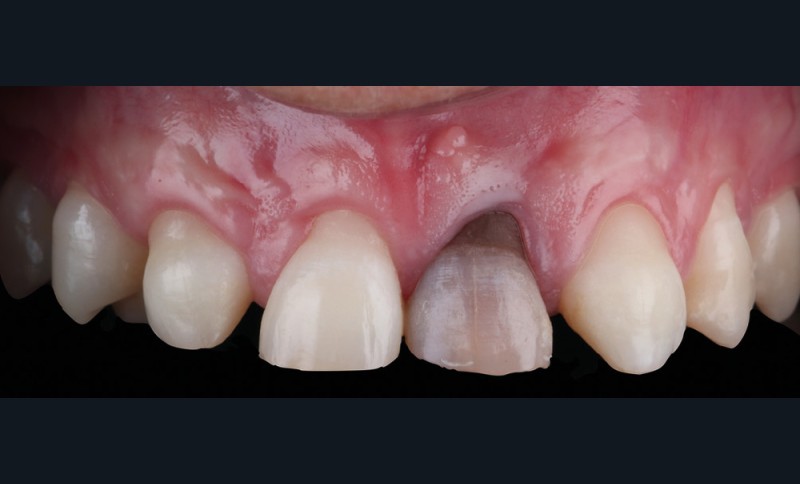

Acte 1 : consultation (fig. 1)

Le patient présente des agénésies génétiques multiples : sur le secteur maxillaire antérieur, il lui manque les deux latérales 12 et 22 ainsi que la canine droite 13 (fig. 1).

Celle du visage d’abord, qui met en évidence un décalage des axes importants : la ligne horizontale maxillaire et la ligne bipupillaire sont loin d’être parallèles. La ligne interincisive part en diagonale, induisant un effet largement inesthétique [2].

L’analyse du sourire du patient révèle une difficulté supplémentaire : haute, la ligne du sourire expose les collets et la gencive, ce qui rend le cas complexe.

Au niveau endobuccal sont observés un défaut des proportions dentaires et une dyschromie importante sur 21.